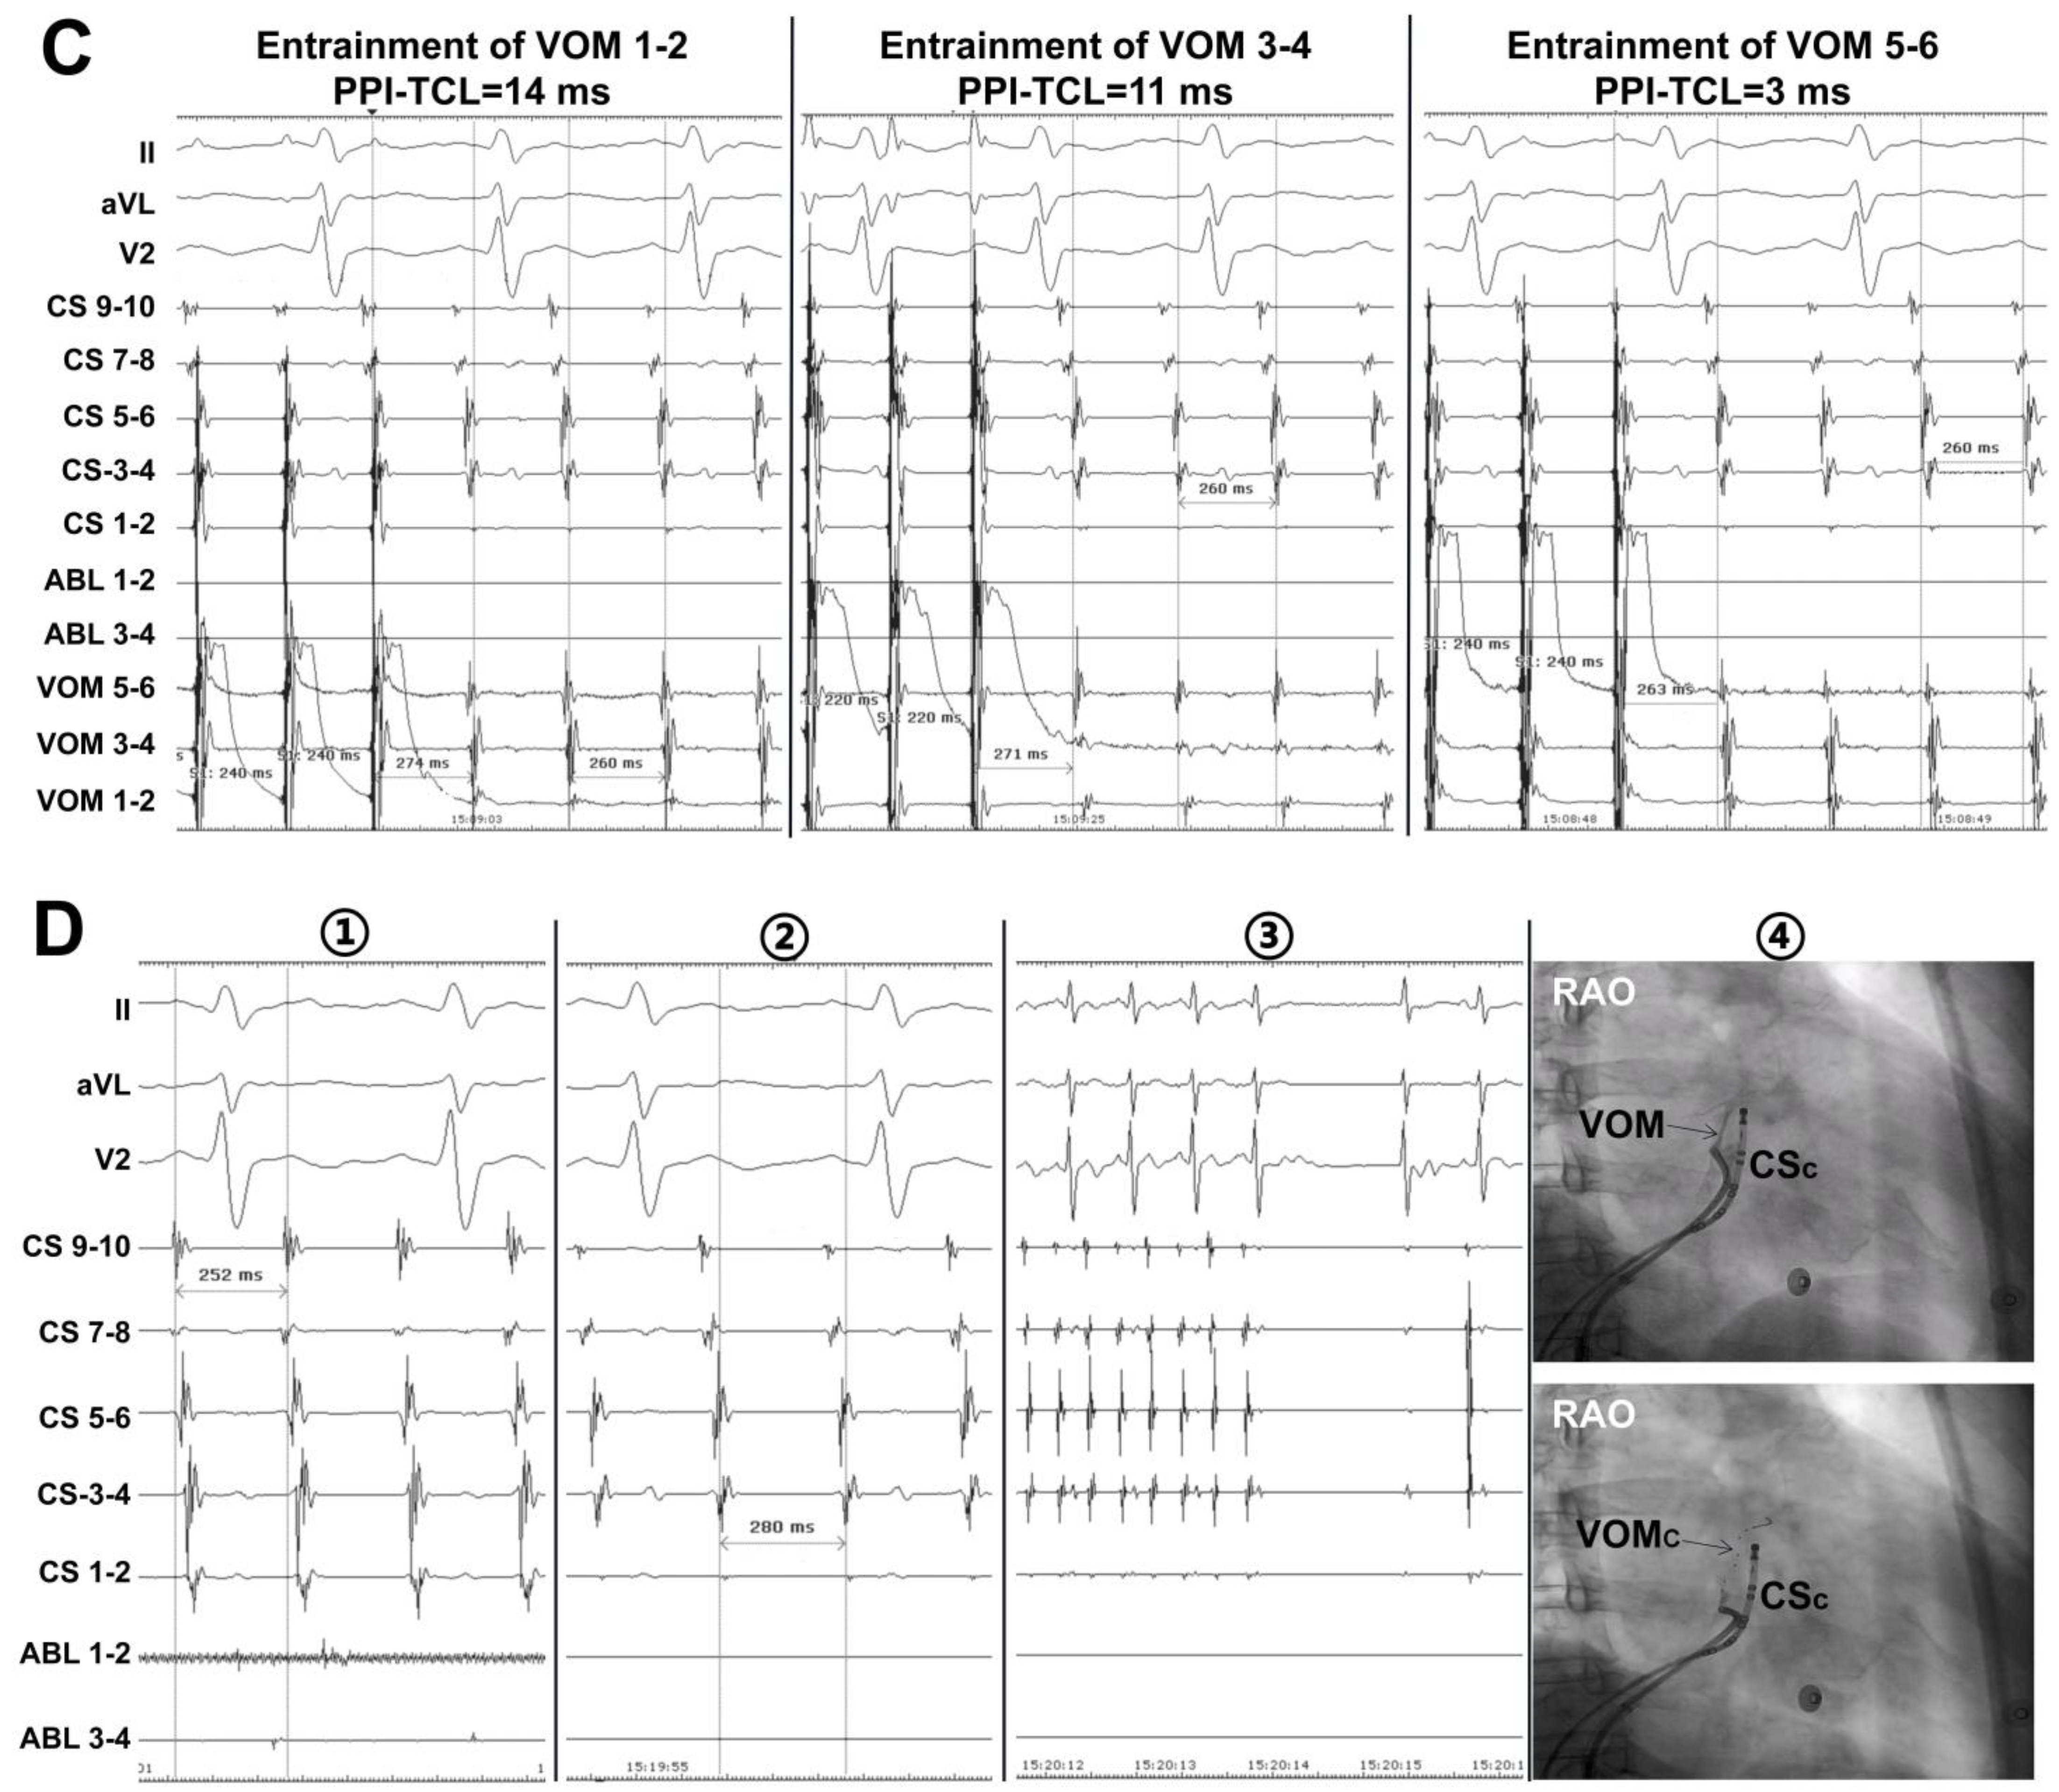

7. The Role of VOM Ethanol Infusion in PeAF Ablation

8. Technique for VOM Ethanol Infusion